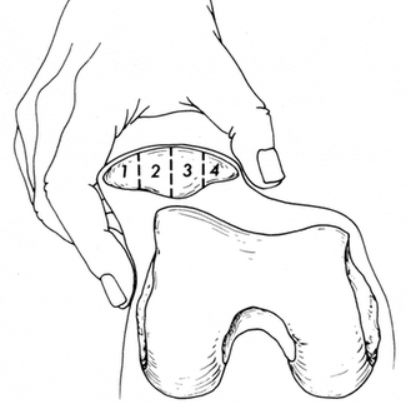

관절경: 진단이 어렵거나, 수술을 목적으로 할 때 시행되는 검사로, 관절 안을 직접 카메라로 보면서 연골의 변화 정도를 확실히 판단할 수 있습니다. 그러나 비침습적 진단법이 우선 시행됩니다.

관절경 수술로 손상된 연골 부위를 절제하거나 연골 아래 뼈에 작은 구멍을 내어 재생을 유도합니다.

무릎뼈 관절면을 정리하거나 관절 내 반월상 연골판 이상이 있으면 부분 제거술 및 봉합술을 시행하기도 합니다.